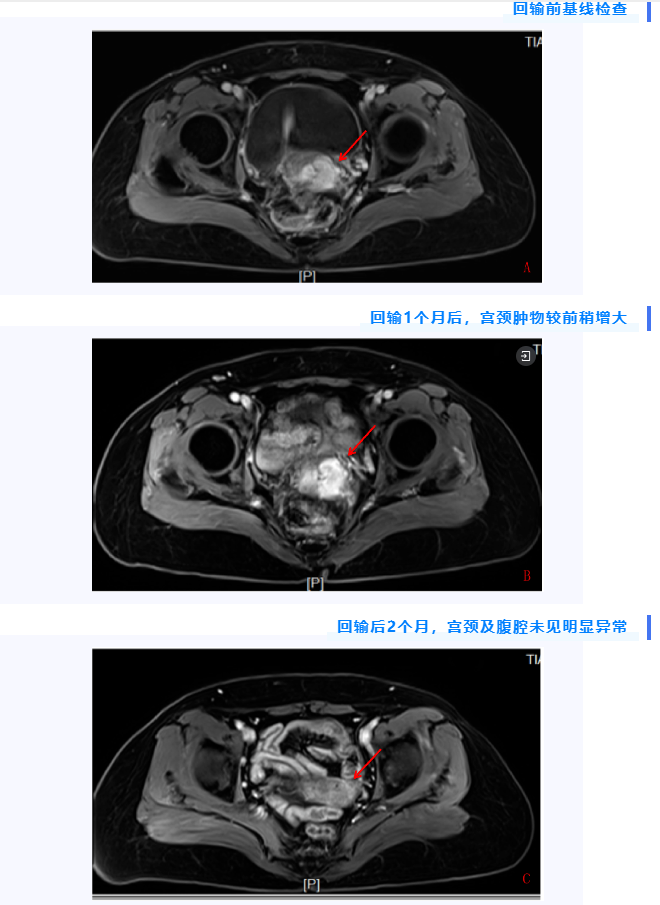

回输后,患者自觉食欲减退、消化不良等症状较前明显缓解。回输后1个月,患者复查全腹部增强MRI,提示宫颈软组织肿物较回输前稍增大(假性进展),但1个月后再次复查全腹部增强MRI,宫颈未见明显异常。患者疗效达到完全缓解。截至发稿日,患者每月影像学复查,已达到CR,即完全缓解(complete response),无病生存期现已超过8周。 TIL(Tumor Infiltrating Lymphocytes,肿瘤浸润淋巴细胞)是一种从肿瘤组织中分离出的浸润淋巴细胞。这些淋巴细胞中有部分是针对肿瘤特异性突变抗原的T细胞,是深入到敌军内部打击能力最强的免疫细胞,被认为是一种机体对肿瘤细胞特异性免疫反应。 TIL疗法是从肿瘤附近组织中分离出TIL细胞,加入生长因子IL-2进行体外大量扩增,再回输到患者体内,从而扩大免疫应答,治疗原发或继发肿瘤的方法。这种疗法利用能够识别并靶向患者肿瘤的T细胞作为攻克癌症的免疫大军回输到体内,是根据每个癌症患者量身定制的个体化抗癌疗法,具有多克隆化,可特异性识别多种新生抗原,个体化,高度特异性,持久性,输注后可形成免疫记忆等特点。 TIL细胞疗法与其它新的免疫疗法的区别 肿瘤的DC,NK细胞疗法已经为大家所熟知,而TILs与CAR-T,TCR-T是基于T细胞的三大疗法,是完全不同于传统细胞疗法的一类新型疗法。其中TILs疗法又是一种赶超CAR-T的新型实体瘤T细胞疗法, 首先,TIL的免疫细胞来自于肿瘤组织,而其他细胞免疫疗法大部分来取自血液。据估计,肿瘤里分离出的免疫细胞,有60%以上能识别肿瘤,而血液里面分离的免疫细胞,不到0.5%。这直接决定了免疫细胞识别肿瘤的能力。 其次,这种新型的疗法不是像传统的简单的扩增回输,而是要确定患者病例中特定的突变。之后利用突变信息找到能够最有效瞄准这些突变的T细胞,最后提取出专门患者肿瘤中细胞突变的T细胞,这些细胞具有精准识别癌细胞的能力。相比之下,CAR-T和TCR-T中用于治疗的T细胞是通过基因转染技术改造的外周血T细胞,是进行修饰而非筛选培养,因此,精准识别的能力与TIL细胞相差甚远。 最后一点,TILs疗法扩增数量庞大。TILs细胞经过分离筛选后,会加入白细胞介素2进行培养,增加免疫细胞存活的几率,最大限度的扩增免疫细胞,达到数百亿~数千亿级别,确保T细胞的有效性和活性后重新注入到患者体内,这意味着体内的抗癌“兵力”大大增强。 据专家介绍,TIL疗法专供实体瘤,包括但不限于晚期癌症,只要是肿瘤形成可取样,就适合该疗法。尤其是早期可手术患者,在术后辅助领域更有良好的高效低毒优势。在术后防复发领域更值得期待。